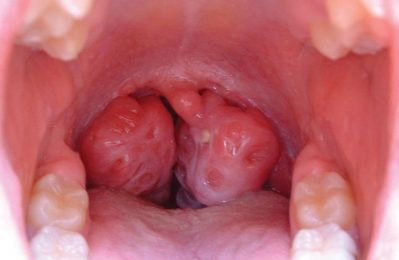

Bã đậu amidan là tình trạng khá phổ biến, khiến nhiều bà con lo lắng khi gặp phải. Tuấn tôi thường thấy người bệnh than...